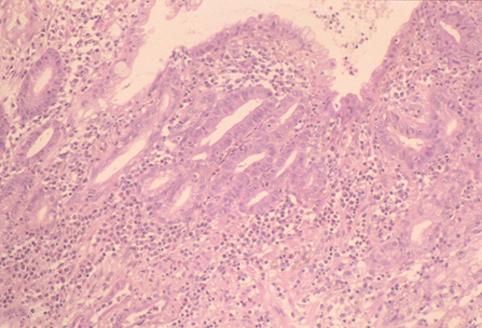

Criteria of Hist.ClassificationMalignant epithelial tumor/Adenocarcinoma

LocationStomach/Body

Macroscopic TypesType 0/IIc (IIc) Superficial depressed type

Size10 - 14

Depth of Tumor Invasionmucosa